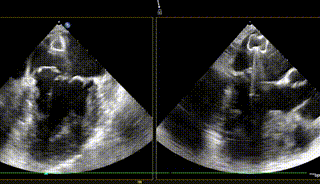

跨瓣球,跨瓣,方位练习,进鞘

在MultiVue下定位与夹合

反流基本消失

该患者为原发性二尖瓣反流患者,病变位置偏P3+PC。目前国内外专家对该类非典型病例患者的TEER治疗尚刚刚起步。由于非2区病变患者瓣膜反流位置较偏,操作器械系统输送到达目标位置困难、同时长轴切面与实际夹臂存在夹角,需要使用具有MultiVue(三维重建)功能的超声机器,且手术中缠绕腱索的风险增大,该类患者往往在筛选期就被拒绝难以得有救治,而ValveClamp系统通过心尖操作,选取最佳穿刺点,仅40分钟就植入1枚夹子,术后几乎无反流,充分显示器械操作便利性、高效性。该例手术的成功,标志着河南省二尖瓣反流经导管介入治疗方面取得新突破,该技术未来将造福更多省内二尖瓣反流患者。